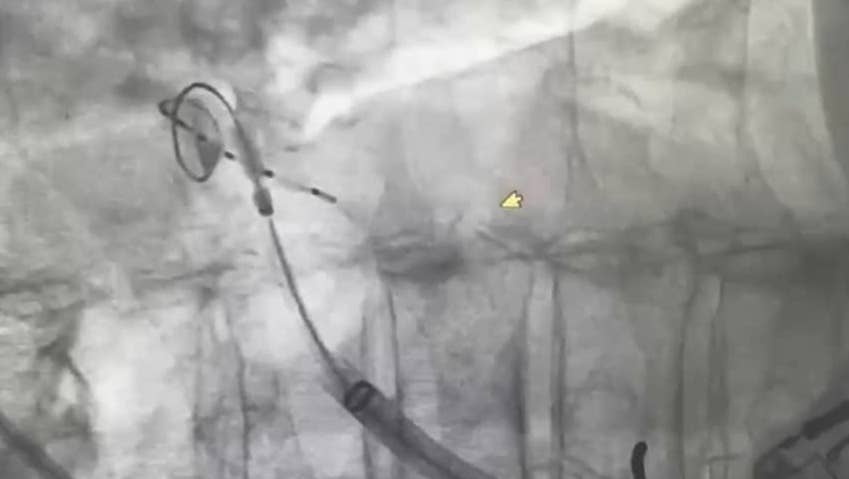

Cryoballoon Ablation is a groundbreaking treatment for AFib that uses extreme cold to isolate pulmonary veins, the origin of abnormal electrical signals. By combining this technique with ICE, the procedure ensures greater accuracy and safety, providing patients with fewer complications and faster recovery. This seamless integration of innovation transforms patient care while highlighting KPJ Kluang's commitment to excellence.

Dr. Ng Kim Fong, KPJ Kluang’s cardiologist, highlighted its significance, stating, “Cryoballoon Ablation, enhanced with ICE technology, represents a paradigm shift in treating AFib. By allowing real-time imaging of critical areas, such as the interatrial septum, we ensure a safer and more precise procedure. This innovation not only achieves excellent outcomes but also eliminates the need for patients to travel far for advanced care, bringing world-class treatment to KPJ Kluang.”

Cryoballoon Ablation offers significant advantages, including shorter procedure times, reduced risk of complications, and faster recovery. The integration of ICE technology provides real-time imaging during the procedure, further enhancing precision and safety.